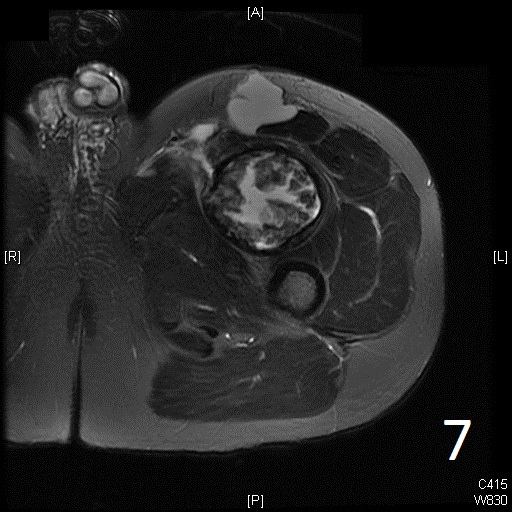

• 60% of fibrosarcomas are intramuscular (Fig. 2, 3, 5, 6, 7, 8)

• Well defined heterogenous mass on T2W (Fig. 4, 9)

• Necrosis and hemorrhage are common, especially in high grade tumors

• On gadolinium, viable areas of tumor enhance, while areas of significant necrosis and hemorrhage do not enhance (Fig. 6).

Fig. 5-9: Axial and sagittal (Fig. 6) MRI shows a fibrosarcoma in the proximal quadriceps muscle that is isointense to muscle on T1W images, and a heterogeneous on T2W FS (Fig. 7, 8). The patient was treated with preoperative chemotherapy and the mass underwent extensive necrosis. The mass does not show any enhancement with contrast due to the extensive necrosis. There is only peripheral enhancement with contrast on T1W FS (Fig. 9).